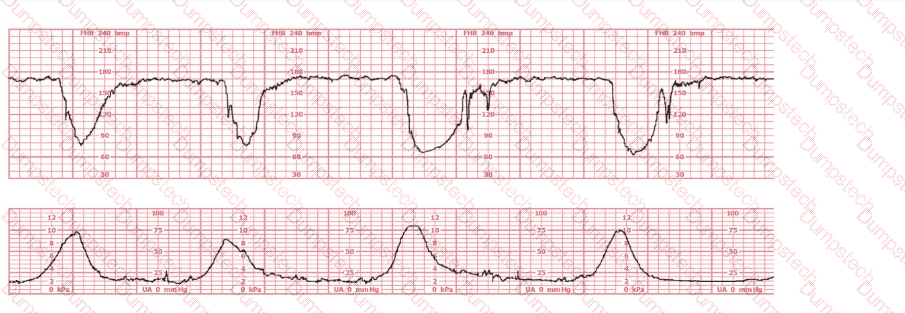

A woman has been 5 cm dilated for the past 3 hours. The tracing shown has developed over the last 30 minutes. The best initial course of action is to: